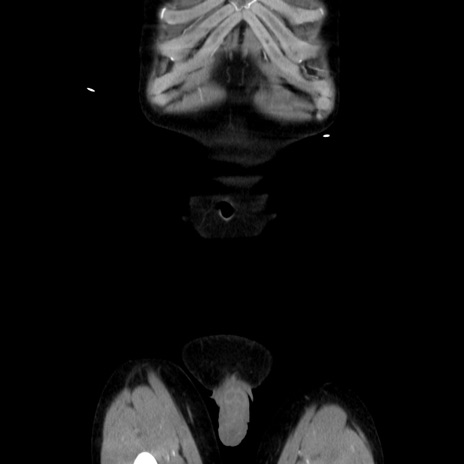

横断像

【症例】40歳代 男性

【主訴】腹痛

【現病歴】4時間ほど前に電車に乗車中に臍部上より腹痛出現。徐々に増悪し起立困難となり、救急外来受診。生ものは数日食べていない。今朝お雑煮を食べた。

【身体所見】BT 36.8℃、BP 117/84mmHg、HR 91/min、SpO2 97%、苦悶様、腹部:臍上部広範囲圧痛あり、反跳痛±

【データ】WBC 8100、CRP 0.03